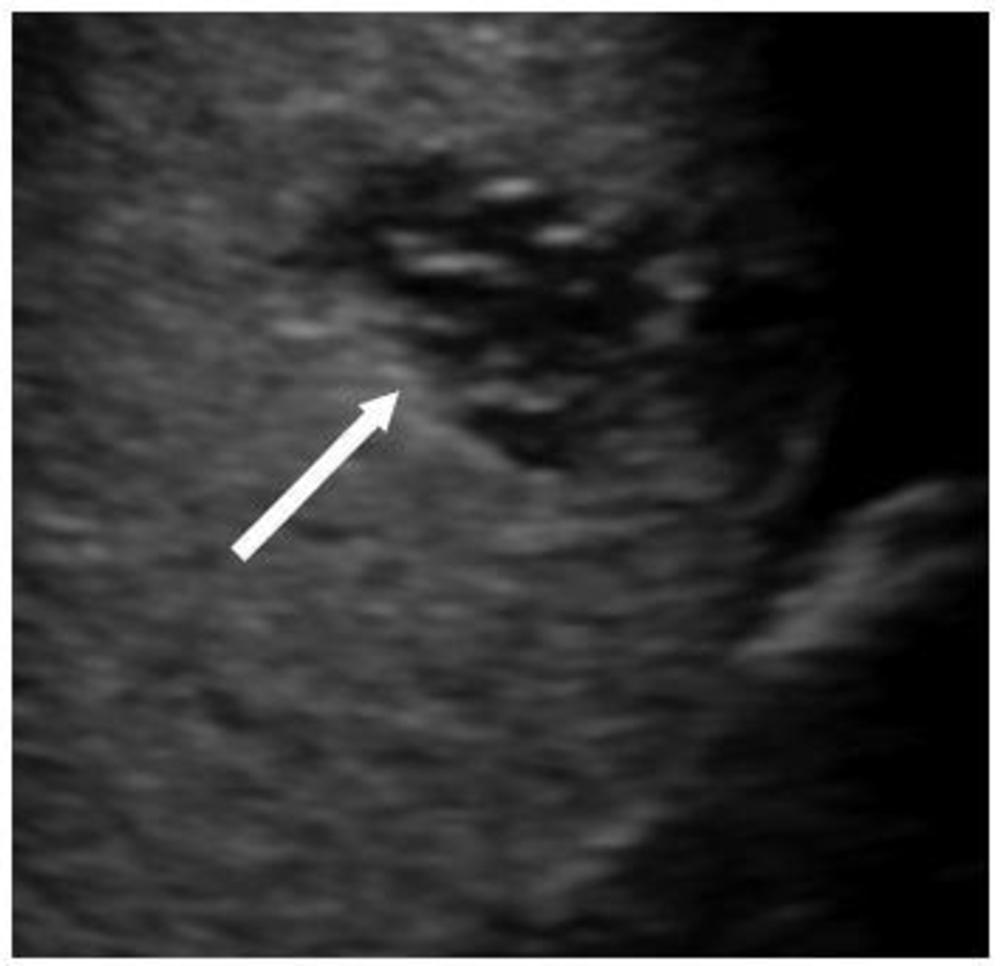

Figure 6. 15 year-old boy with MIS-C. US shows a well-defined subcapsular hypoechoic splenic lesion (arrow) felt to be likely an infarct as the clinical course did not conform with this being a splenic abscess, the main other differential diagnosis for this appearance.